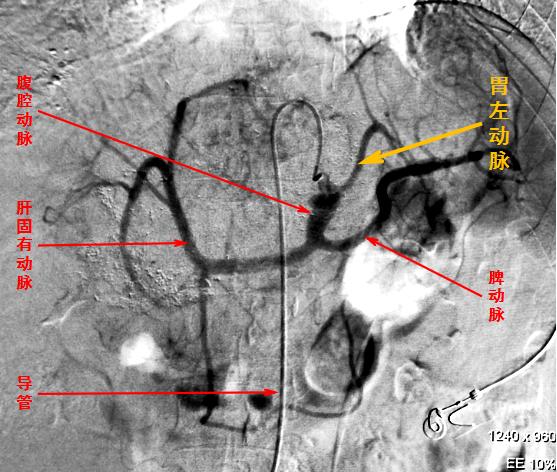

目前,有关介入减肥的理论已经确立,动物实验和初步临床应用已经完成。其基本做法是通过微创介入的方法,插管到患者的胃左动脉,对其实施栓塞。原理在于抑制生长素释放肽(或称饥饿素,能刺激食欲的激素)的产生。人不觉得饿了,不那么想吃了,自然会收获减肥的效果。

“胃左动脉栓塞术”是治疗上消化道出血的常用方法,对于介入医生来说没有什么技术难度。国外学者通过回顾性研究,发现胃左动脉栓塞术在有效止血的前提下,竟然有降低患者体重的“副作用”。受到启发后,我国著名的介入专家滕皋军教授于2011年成功地进行了动物试验,并于2016年5月开始进行了严格而科学的人体研究,证实介入减肥确实有效,还能改善脂肪肝症状,而且很安全,没有出现严重并发症(只栓塞这根血管不会引起胃的缺血坏死)。

胃左动脉与相关动脉造影图示